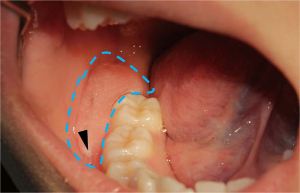

In the model group, the drainage plug completely fitted the postoperative cavity without gaps (Figure 3). One end of the drainage tube passed straight into the cyst cavity [Figure 4, obturation part (OP)], and the other end opened in the mouth lateral to the gum [Figure 4, retention part (RP)] to ensure the timely drainage of cyst effusion. With the drainage plug, the recovery time of patients was effectively shortened, and the postoperative care time was also greatly reduced.